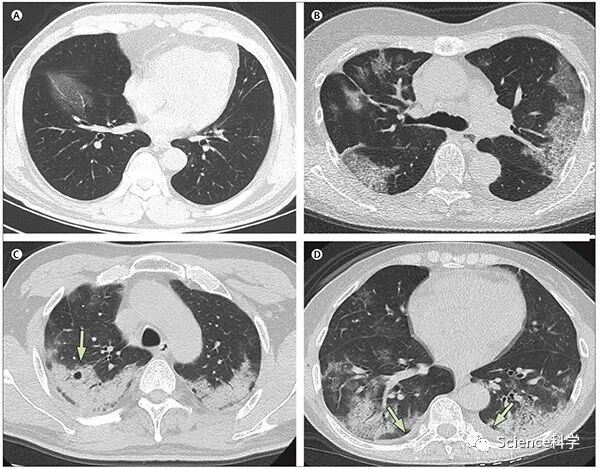

(A)56岁男性,发病第3天;(B)74岁女性,发病第10天;(C)61岁女性,发病第20天;(D)63岁女性,发病第17天。

第1组(n=15)主要表现为单侧(9,60%,)、多中心(8,53%)磨玻璃影(14,93%)。第2组(n=21)病变多为双侧(19,90%)、弥漫性(11,52%)磨玻璃影(17,81%)。此后,磨玻璃影持续减少(第3组17/30,57%;第4组5/15,33%),实变和混合型病变为第3组、第4组患者的主要CT表现(第3组12/30,40%;第4组8/15,53%)。

总体而言,新冠肺炎患者的胸部CT显示肺浸润性病变,甚至出现在无症状患者中。发病1-3周内,病变迅速从单侧、局灶性病变进展为双肺弥漫性磨玻璃影,后期合并实变。